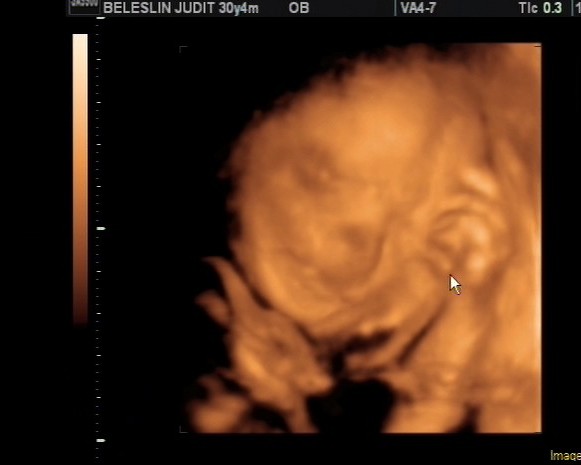

), és este 11 körül elkezdődtek a fájások (13,12,11 percesek). Gyorsan elszaladtam zuhanyozni, és mire végeztem, már 5 percesek lettek. Megvártuk, míg ideér Emőke férje (ő vigyázott Marcira, amíg Anyuék felértek), és elindultunk a kórházba. Mire 0.15-re beértük, már 3 ujjnyi volt a méhszáj. Egészen addig teljesen elviselhető fájásaim voltak, de 01.30-kor burkot repesztett a doki. Na, az azt követő 2 óra szinte elviselhetetlen volt, de 03.25-kor előbújt a kisfickó. Azonnal felsírt, lepisilt mindenkit, 10/10-es apgart kapott. Péter végig bent volt, ő vágta el a köldökzsinórt.